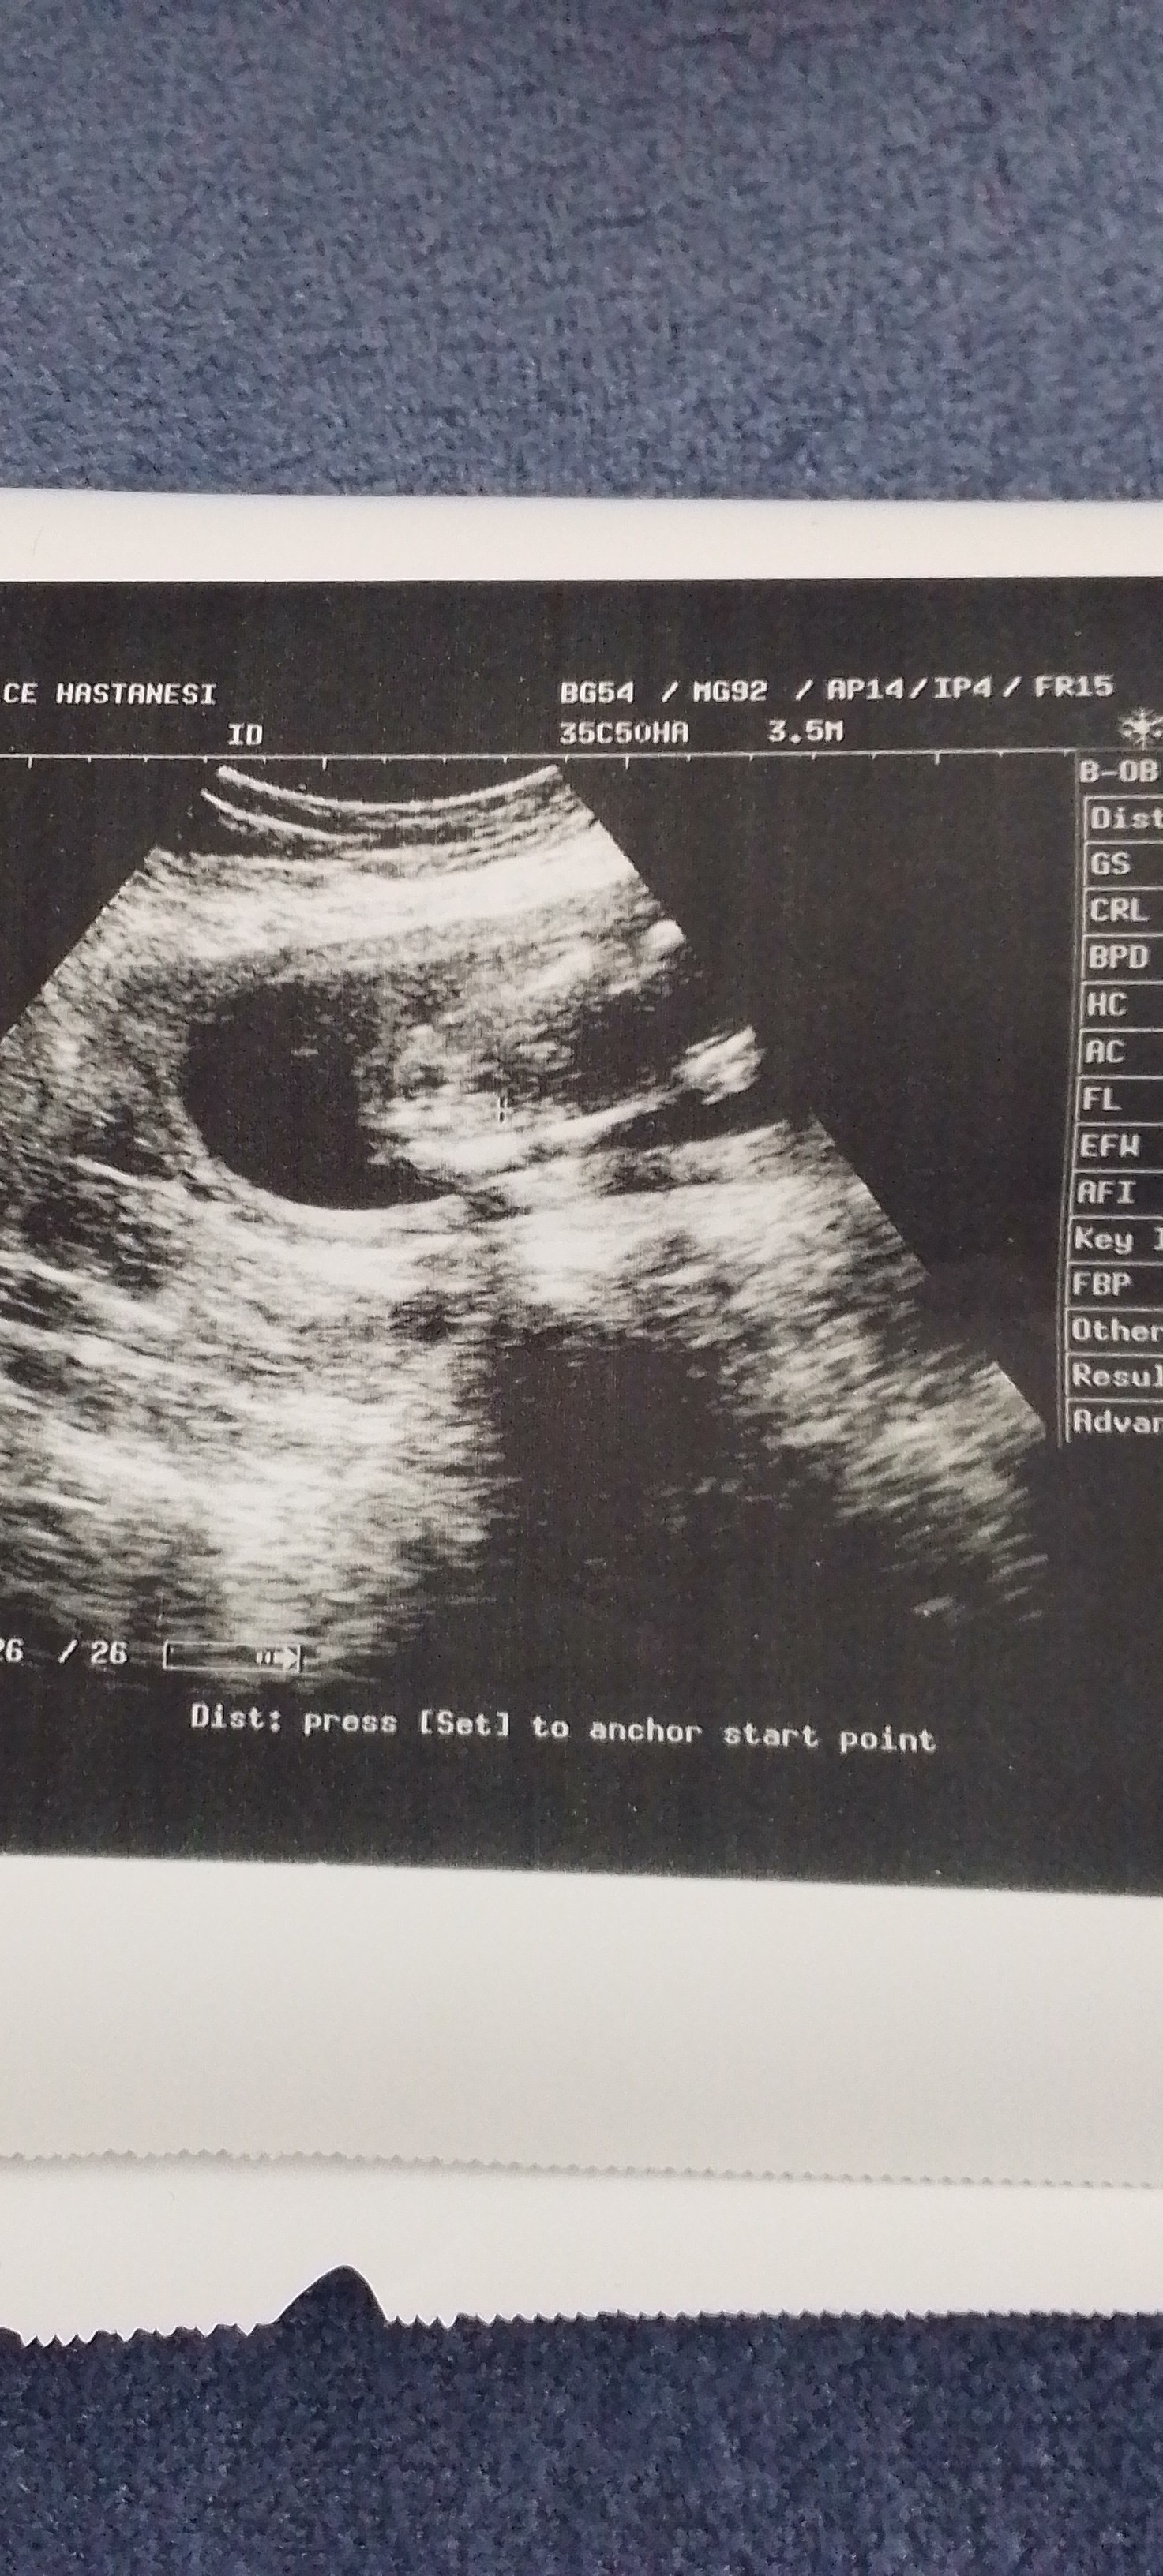

3. 18 hafta cinsiyet iki bacak arası

18 hafta cinsiyet iki bacak arası

Doktor erkek benziyor dedi ama net bişey demedi iki bacak arası resmini verdi anliyanlar